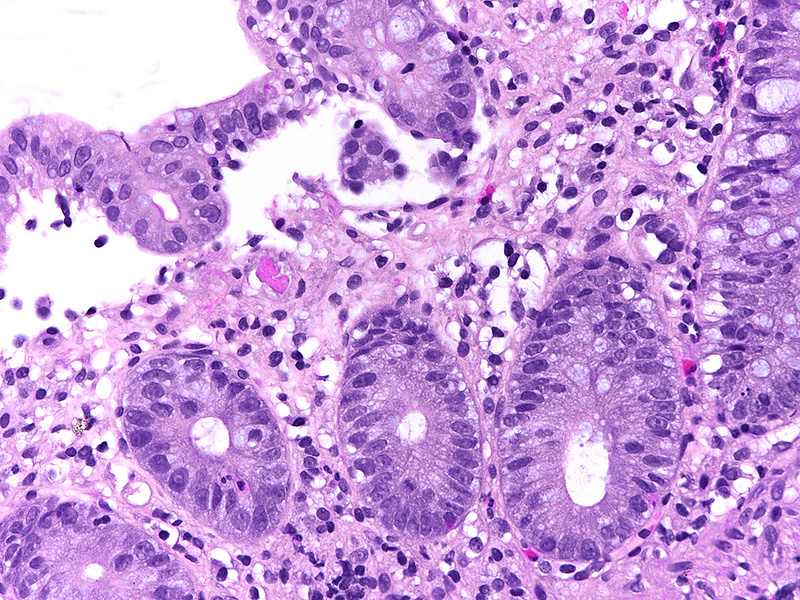

Biopsy material from the right colon in a 48-year-old male.

NSAID colonopathy.

Histologically, the architecture of the mucosa showed mild architectural distortion. The cell content within the mucosa was increased, with predominance of monuclear cells, that is, lymphocytes and plasma cells (Panels A-B). High magnification revealed mild basal plasmactytosis and additional neutrophil granulocytes in stroma and crypt epithelium (cryptitis) as well as clusters of eosinophils (Panel C). The crypt epithelium showed reactive changes, with loss of goblet cells, variation in nuclear size with small nucleoli, and increased apoptosis. Withered crypts were only occasionally seen (Panel D). Superficial erosion and regenerative epithelium were identified in the coecum (Panel E), with rare superficial intracapillary fibrin thrombi (Panel F).